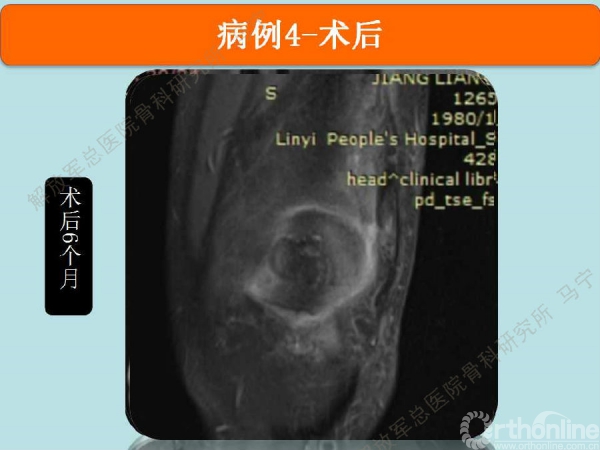

术后6个月复查MRI,软骨修复的已经具备一定的厚度,软骨下骨没有明显水肿。增生的软骨下骨被去除后没有再进一步磨损滑车软骨。